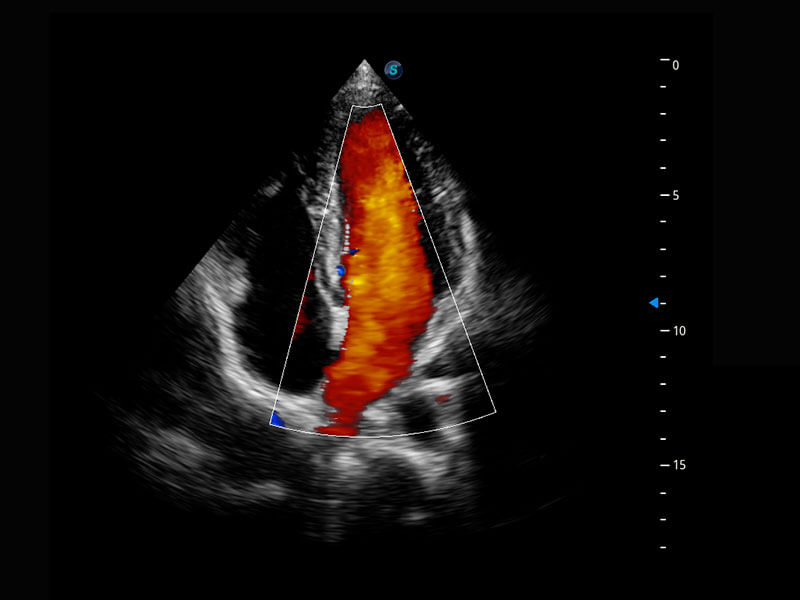

四腔切面

四腔心血流

P60搭载一系列胎儿心脏成像技术,实现精细的胎儿心脏评估。